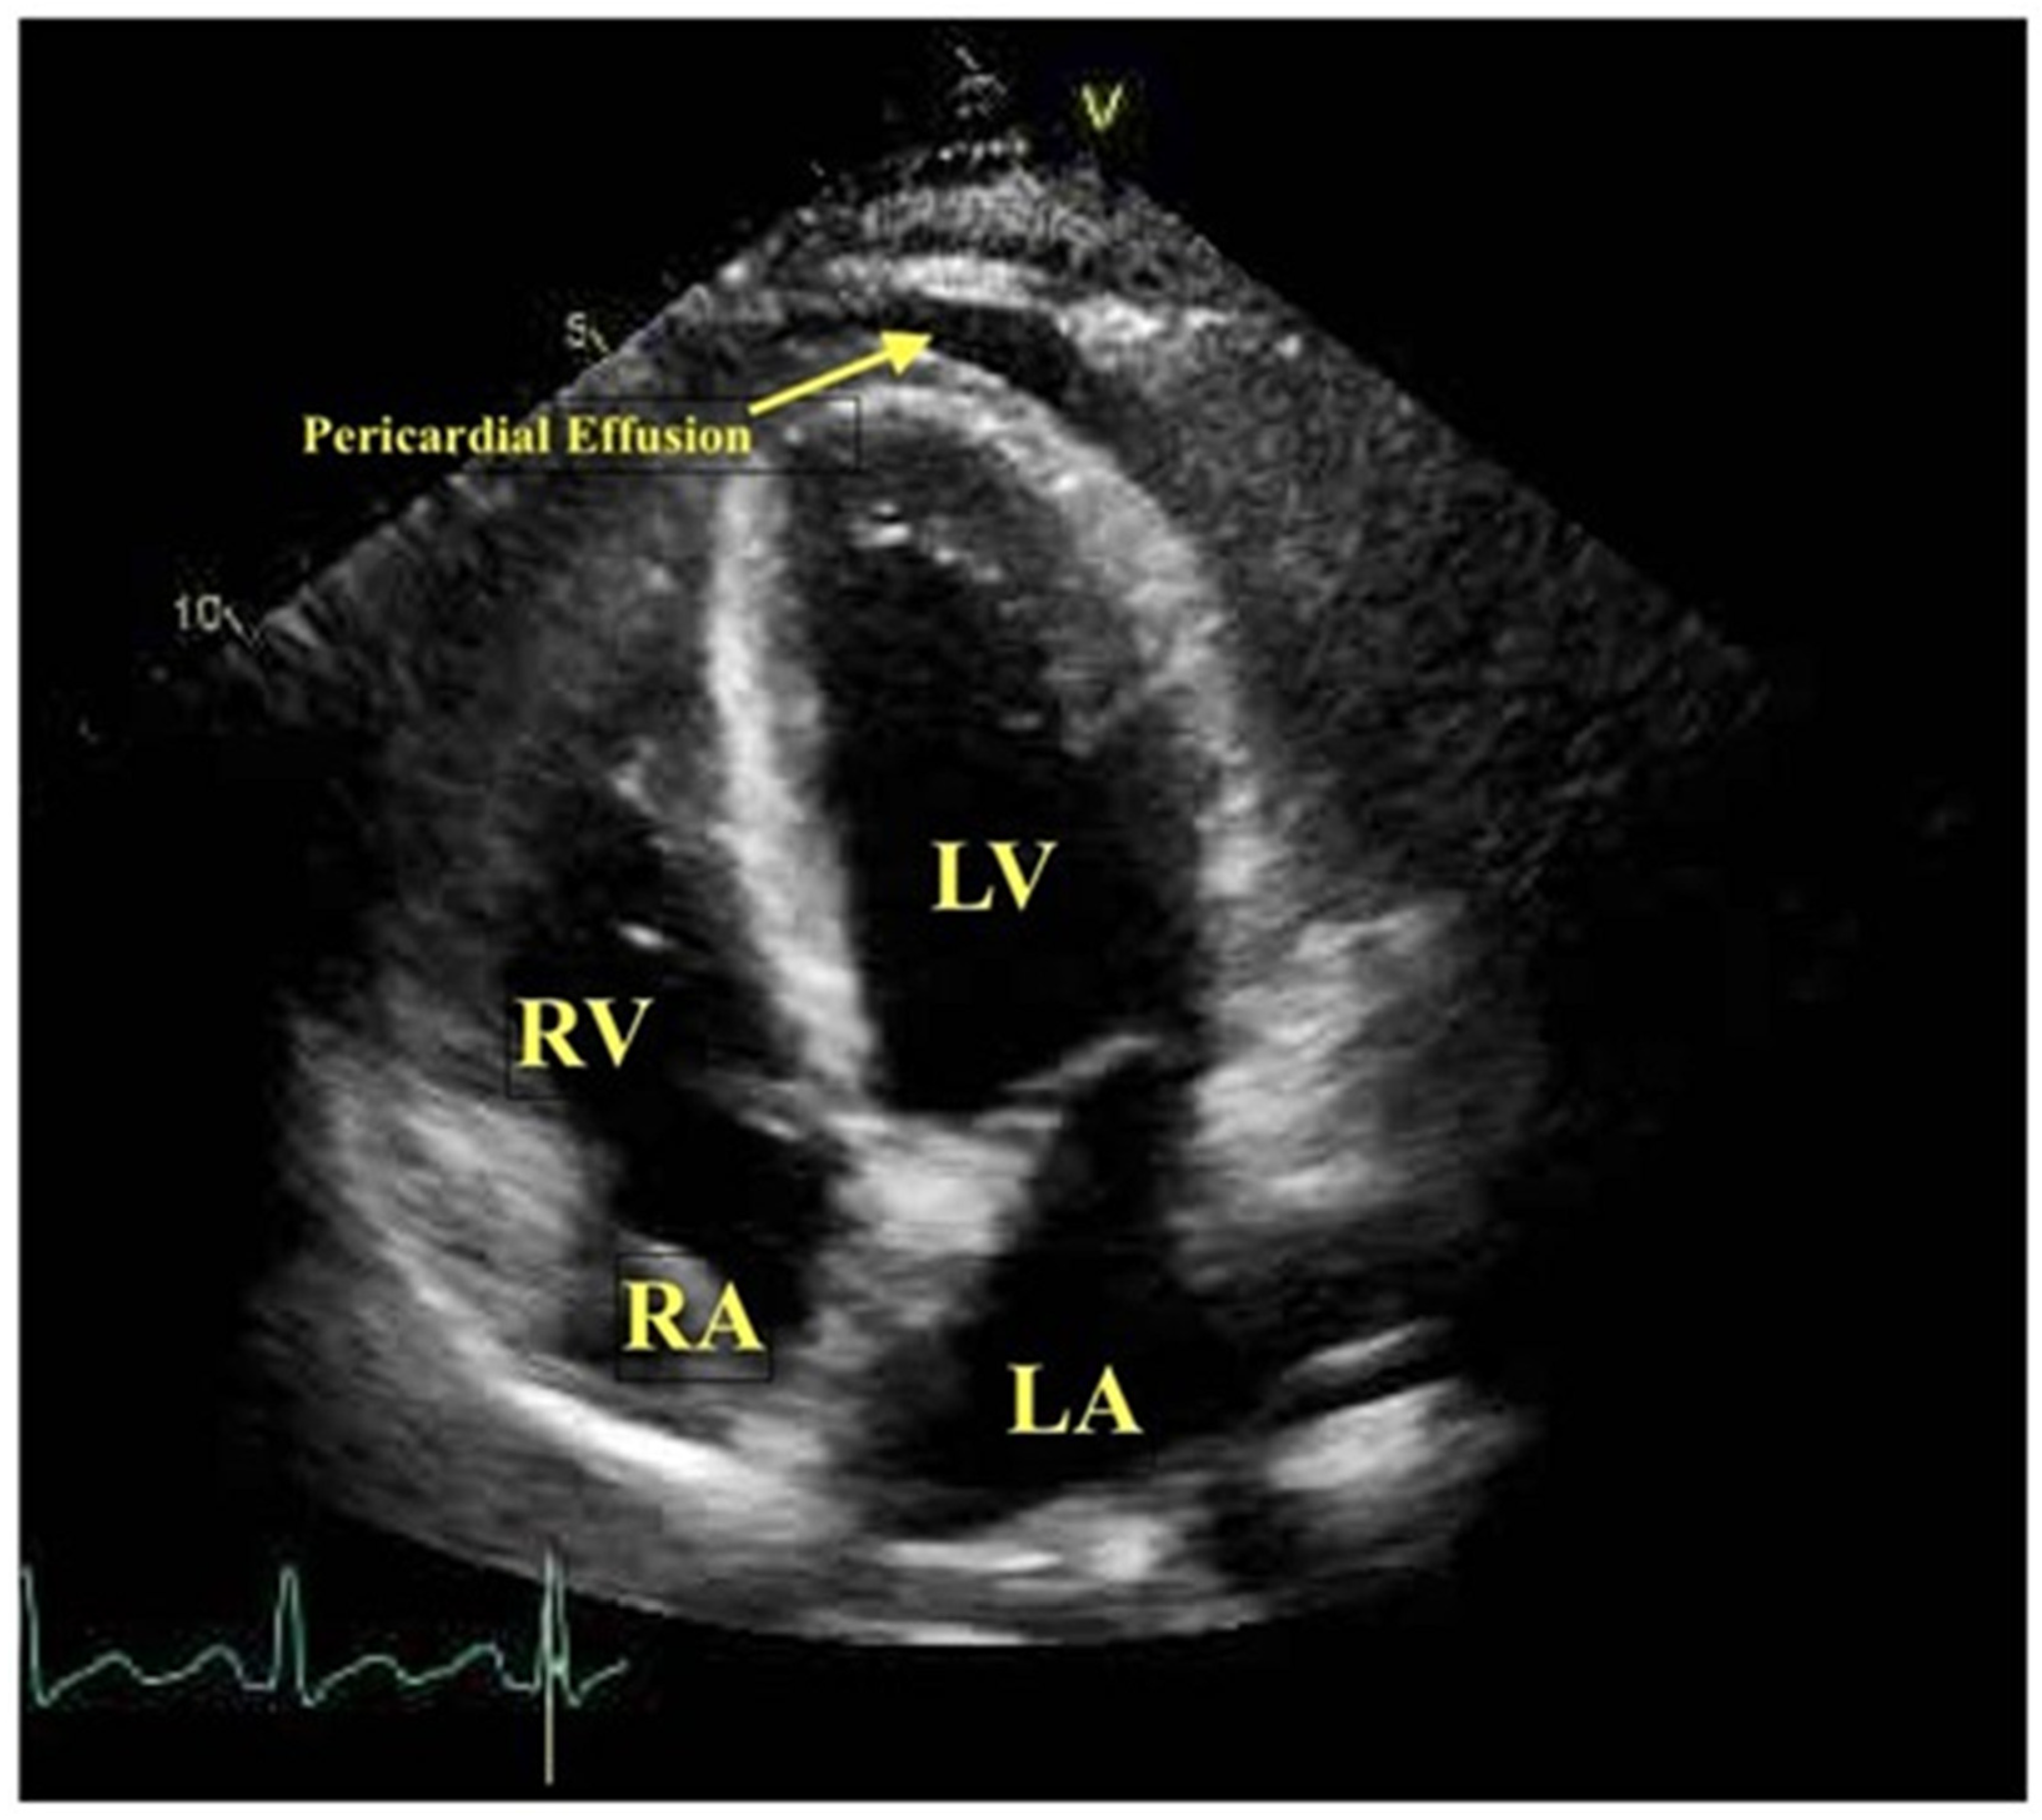

2.1.1. Two-Dimensional Transthoracic Echocardiography